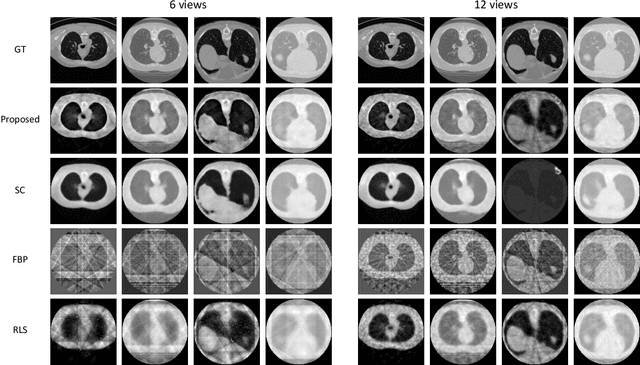

Abstract:Reconstruction of few-view x-ray Computed Tomography (CT) data is a highly ill-posed problem. It is often used in applications that require low radiation dose in clinical CT, rapid industrial scanning, or fixed-gantry CT. Existing analytic or iterative algorithms generally produce poorly reconstructed images, severely deteriorated by artifacts and noise, especially when the number of x-ray projections is considerably low. This paper presents a deep network-driven approach to address extreme few-view CT by incorporating convolutional neural network-based inference into state-of-the-art iterative reconstruction. The proposed method interprets few-view sinogram data using attention-based deep networks to infer the reconstructed image. The predicted image is then used as prior knowledge in the iterative algorithm for final reconstruction. We demonstrate effectiveness of the proposed approach by performing reconstruction experiments on a chest CT dataset.